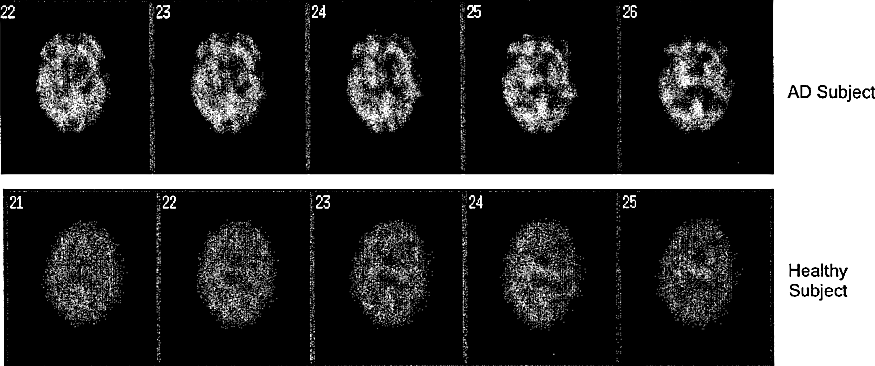

Compounds and amyloid probes thereof for therapeutic and imaging uses